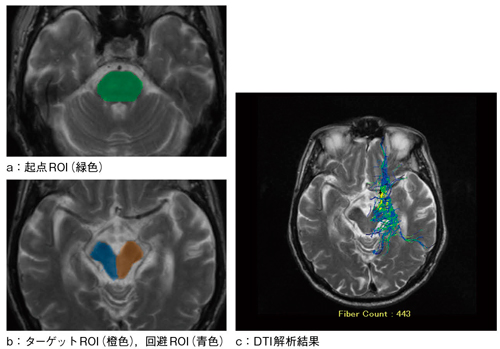

次に,描出しようとする神経線維の走行を考慮し,起点となる位置(図2 a),ターゲットとなる位置(図2 b)にROIを設定する。必要としない領域がトラッキングされることを防ぐために,回避ROIと呼ばれる関心領域を不要な領域に設定し,回避ROIを通る神経線維を計算させないようにする機能もある(図2 b)。

図2 ROIの設定方法

本症例では,aに示すように延髄に起点ROIを設定した。bでは,ターゲットROIを大脳脚の右側に,回避ROIを大脳脚の左側にそれぞれ設定した。cでは,ターゲットROIを設定した大脳脚の右側に拡散テンソルが表示され,回避ROIを設定した左側は拡散テンソルが表示されていない。